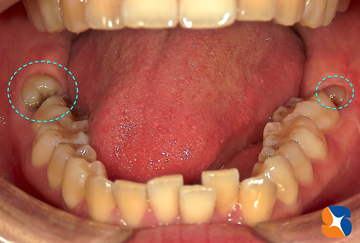

患者様「次、いつ帰ってこれるか分からないので腫れや痛みは覚悟で両方お願いします」とのこと。急きょ、左右、横向き親知らずの難抜歯が始まりました。

治療開始から約1時間、無事に左右の抜歯が終了しました。痛みや腫れを極力抑え、抜歯跡の早期回復を目的に、当院ではテルプラグ(無料)を抜歯跡の穴に入れます。